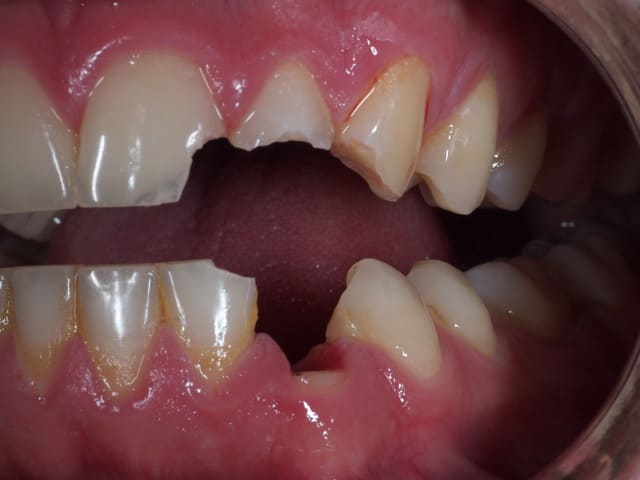

Ne jamais provoquer quelqu'un qui tient un marteau dans sa main !

Putain j'ai mal pour lui juste en regardant la photo.

La lèvre doit être dans un bel état.